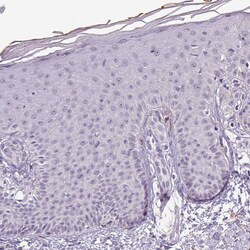

Invitrogen™ Apolipoprotein C1 Polyclonal Antibody

| Immunohistochemistry (Paraffin) | |